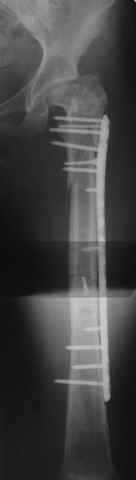

Re: Перелом проксимального отдела диспластичного б

Прошу прощения, со снимками глюк произошел. Высылаю. С уважением Евгений У.

Получилось очень симпатично, мои поздравления. А можно фото конечности без наклеек посмотреть?

И межфрагментарный винт на диафизе - так ли он нужен при выбранном варианте остеосинтеза с относительной стабильностью?

Хотя все-таки закрыто антгерадно заштифтовать тут было вполне можно, и при использовании отечетственного имплантата лечение обошлось бы на порядок дешевле. Опасения коллеги Кульджанова насчет кровоснабжения головки бедра и предстоящих операции в этой области кажуься несколько

преувеличенными - и стержень можно через вертел ввести, да и расстройства кровоснабжения головки, если они случатся после штифтования, не будут длиться вечно.

Но в люом случае, что сделано - то сделано, и сделанное выглядит вполне обнадеживающе, так что еще раз поздравляю коллег с успешным выходом из непростой ситуации.